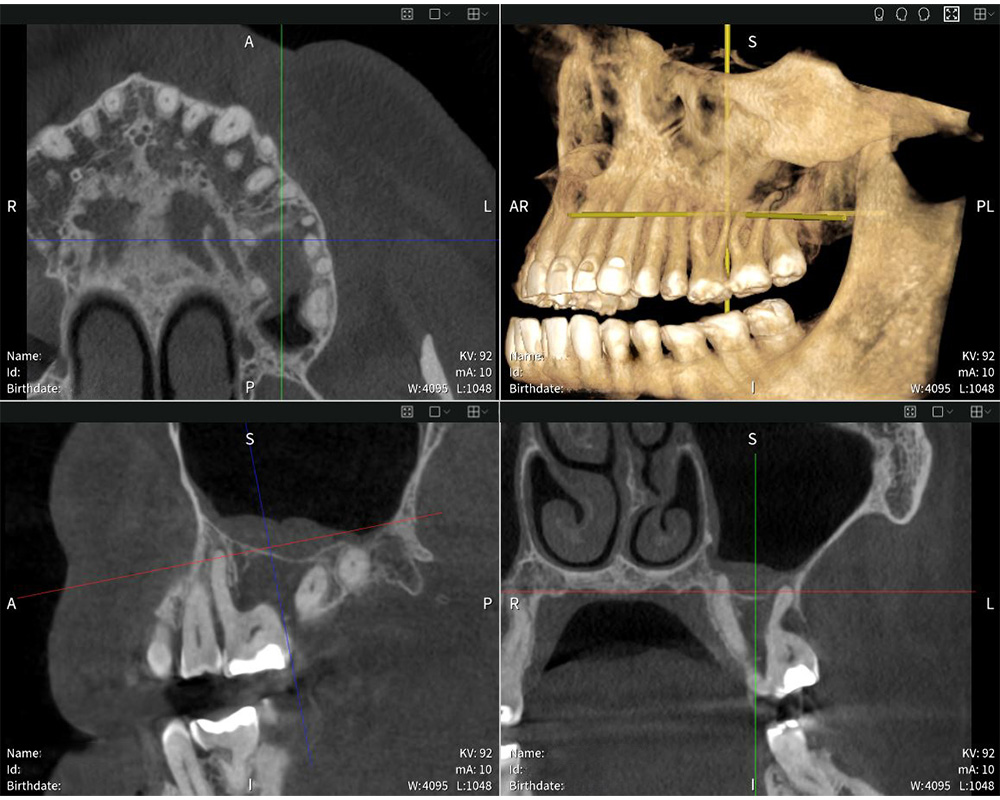

Seethrough Studio garantiza imágenes nítidas, detalladas y sin distorsiones.

Seethrough Studio garantiza imágenes nítidas, detalladas y sin distorsiones. © W&H